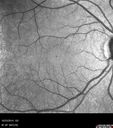

AIDS - HIV Retinopathy - Cotton Wool Spots466 views54-year-old woman HIV positive for 18 years. Her CD4 count is currently less than 50 and she was hospitalized for pneumocystis carinii pneumonia 5 months ago. She has noticed just for the last few weeks a few blind spots in the paracentral vision. Predominantly out of her right eye when she closes her left eye, she sees a few temporal blind spots. VA 20/25 in both eyes.

AIDS - HIV Retinopathy - Cotton Wool Spots462 views54-year-old woman HIV positive for 18 years. Her CD4 count is currently less than 50 and she was hospitalized for pneumocystis carinii pneumonia 5 months ago. She has noticed just for the last few weeks a few blind spots in the paracentral vision. Predominantly out of her right eye when she closes her left eye, she sees a few temporal blind spots. VA 20/25 in both eyes.

AIDS - HIV Retinopathy - Cotton Wool Spots455 views54-year-old woman HIV positive for 18 years. Her CD4 count is currently less than 50 and she was hospitalized for pneumocystis carinii pneumonia 5 months ago. She has noticed just for the last few weeks a few blind spots in the paracentral vision. Predominantly out of her right eye when she closes her left eye, she sees a few temporal blind spots. VA 20/25 in both eyes.